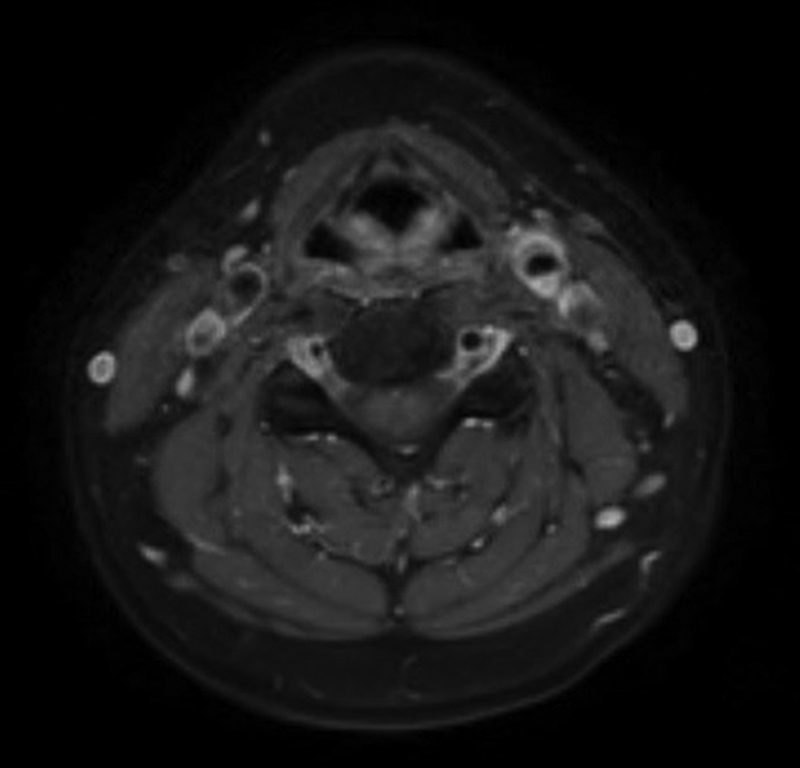

颈动脉短暂性血管周围炎(TIPIC)综合征,历史上曾被命名为特发性颈动脉炎或费氏综合征,是一种以颈动脉炎症和疼痛为特征的罕见疾病。诊断需要特殊的临床放射学表现。我们描述了一名 37 岁女性的病例,她出现头痛和左颈部疼痛,被诊断为伴有暂时性血管周围浸润的 TIPIC 综合征。

Transient perivascular inflammation of the carotid artery (TIPIC) syndrome, historically named idiopathic carotidynia or Fay syndrome, is a rare condition characterized by inflammation and pain in the carotid artery. The diagnosis requires a specific clinical-radiological presentation. We describe a 37-year-old female who presented with headaches and left neck pain and was diagnosed with TIPIC syndrome with temporary perivascular infiltration.